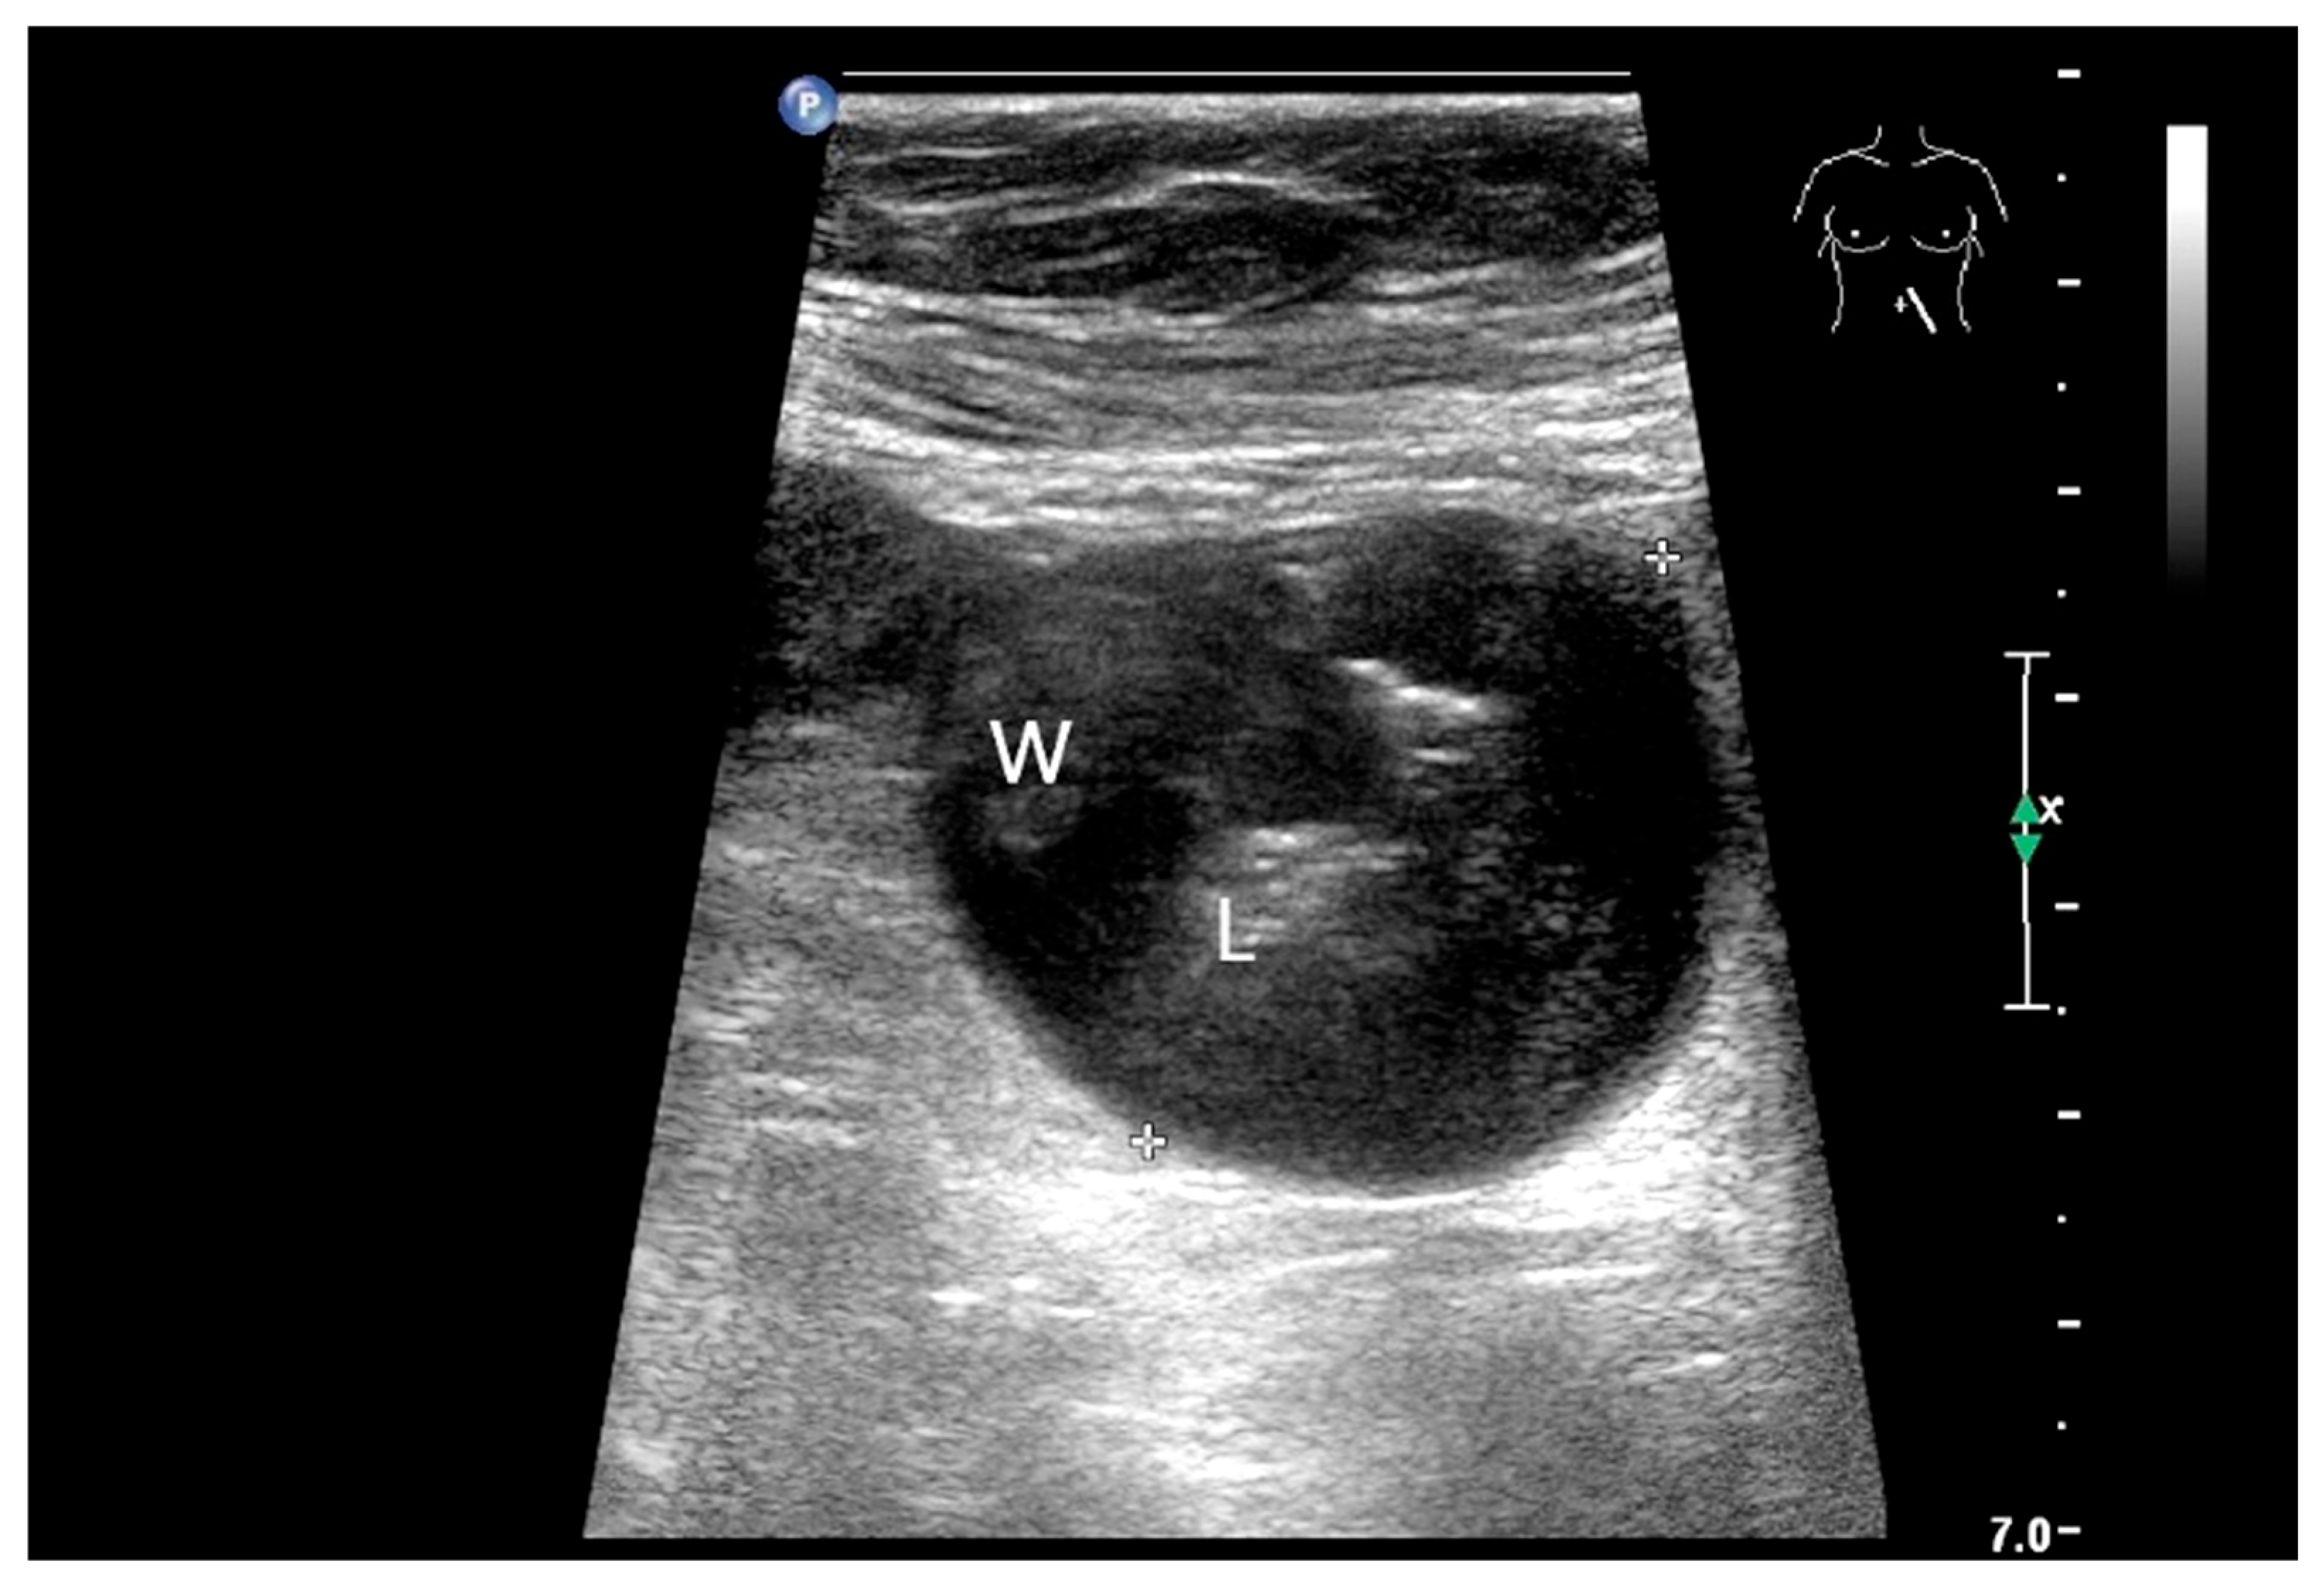

- Schwarze, V.; Marschner, C.; Grosu, S.; Rübenthaler, J.; Knösel, T.; Clevert, D.A. Modern sonographic imaging of abdominal neuroendocrine tumors. Radiologe 2019, 59, 1002–1009. [Google Scholar] [CrossRef] [PubMed]

- Zhao, J.Y.; Zhuang, H.; Luo, Y.; Su, M.G.; Xiong, M.L.; Wu, Y.T. Double contrast-enhanced ultrasonography of a small intestinal neuroendocrine tumor: A case report of a recommendable imaging modality. Precis. Clin. Med. 2020, 3, 147–152. [Google Scholar] [CrossRef]

| Neuroendocrine tumor | Small, nodular hypoechoic wall thickenings, mostly in the submucosa with spreading into the other layers. Usually with small vessels on CDI. Regionally enlarged lymph nodes. Multilocular manifestations are possible. |